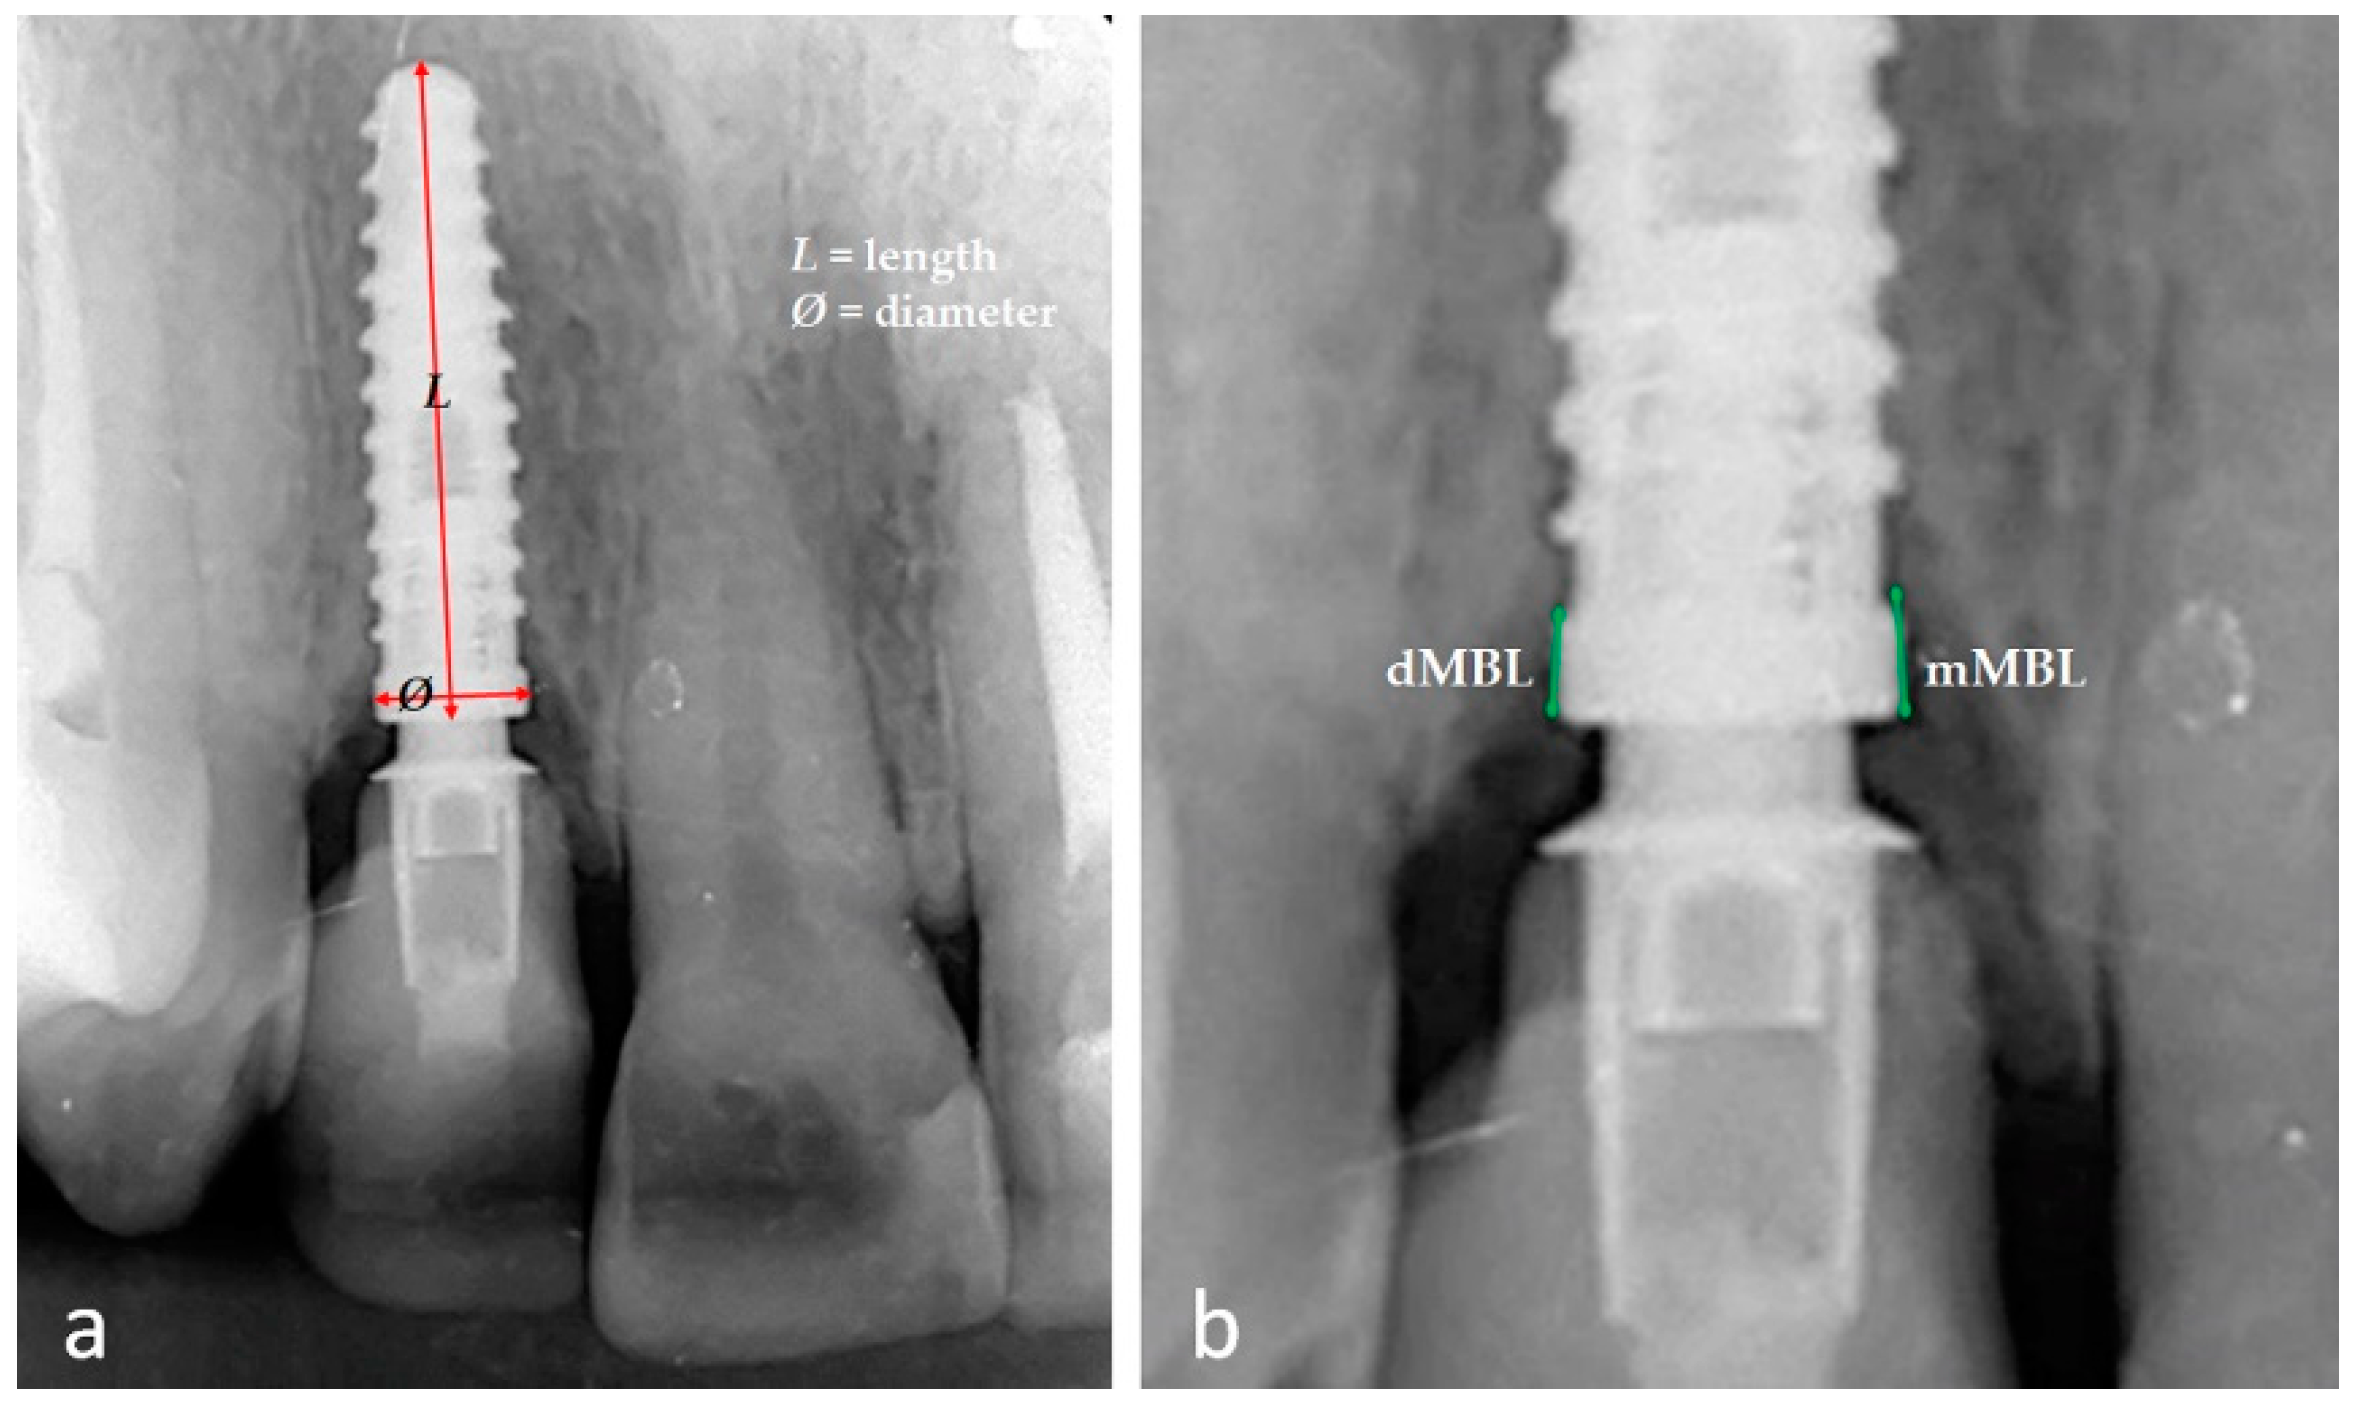

All radiographic images were analyzed using the ImageJ software (National Institute of Health, Bethesda, MD, USA). For calibration before the measurements, the implant dimension (diameter and length) (Figure 3a), reported in the clinical history of each patient, was used as a reference value to adjust for any distortion. Each radiograph image was measured on a medical screen with a resolution of 1920 × 1080 and 10× magnification (Surgical Display Monitors-Medical Imaging Displays, Sony Inc., Tokyo, Japan). The marginal bone level was measured on immediate periapical radiography after installing the definitive crown (baseline) and follow-up. The segment between the implant neck and the first bone-to-implant contact was calculated and considered as both the mesial and distal position for each implant (Figure 3b). The same examiner makes all the measurements with much experience in dental implants and image analysis. Each measurement was repeated 3 times in each position (mesial and distal). These same measurements were repeated after 2 weeks to calculate an average used as reference values and the estimated error margin. The calculated intra-examiner error was, on average 0.05 mm, indicating that the intra-operator error was not statistically significant (p = 0.18 with 95% CI).

Figure 3. Representative image of the calibration using the implant diameter and length (a) and the measurement positions in mesial (mMBL) and distal (dMBL) (b).